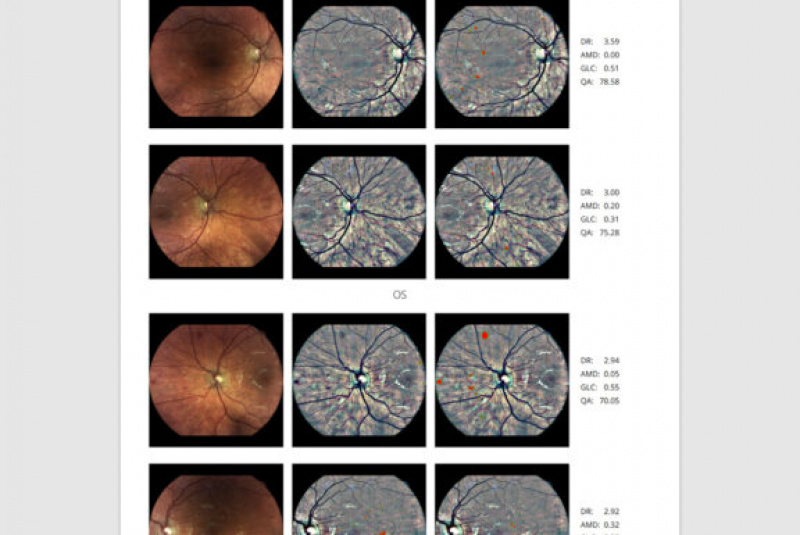

AI (umelá inteligencia) okamžite rozpozná práznaky diabetickej retinopatie a klasifikuje výsledky podľa závažnosti na základe medzinárodných klasifikácií. Získate prehľad s hodnotením závažnosti záchytu, kde po analýze snímok zachytených kamerou iCare DRS Plus je automaticky generovaný report o pacientovi so stupnicou závažnosti pre diabetickú retinopatiu na základe medzinárodných štandardov (ICDR, AREDS).

Fundus kamera iCare DRSplus urobí celkovo 4 vysoko kvalitné True Color snímky (dve z pravého a dve z ľavého oka), ktoré sa automaticky ukladajú na cloud a posielajú sa na spracovanie AI - umelej inteligencii. Report je dostupný ihneď a ten je možné prekonzultovať s pacientom počas tej istej návštevy u lekára.